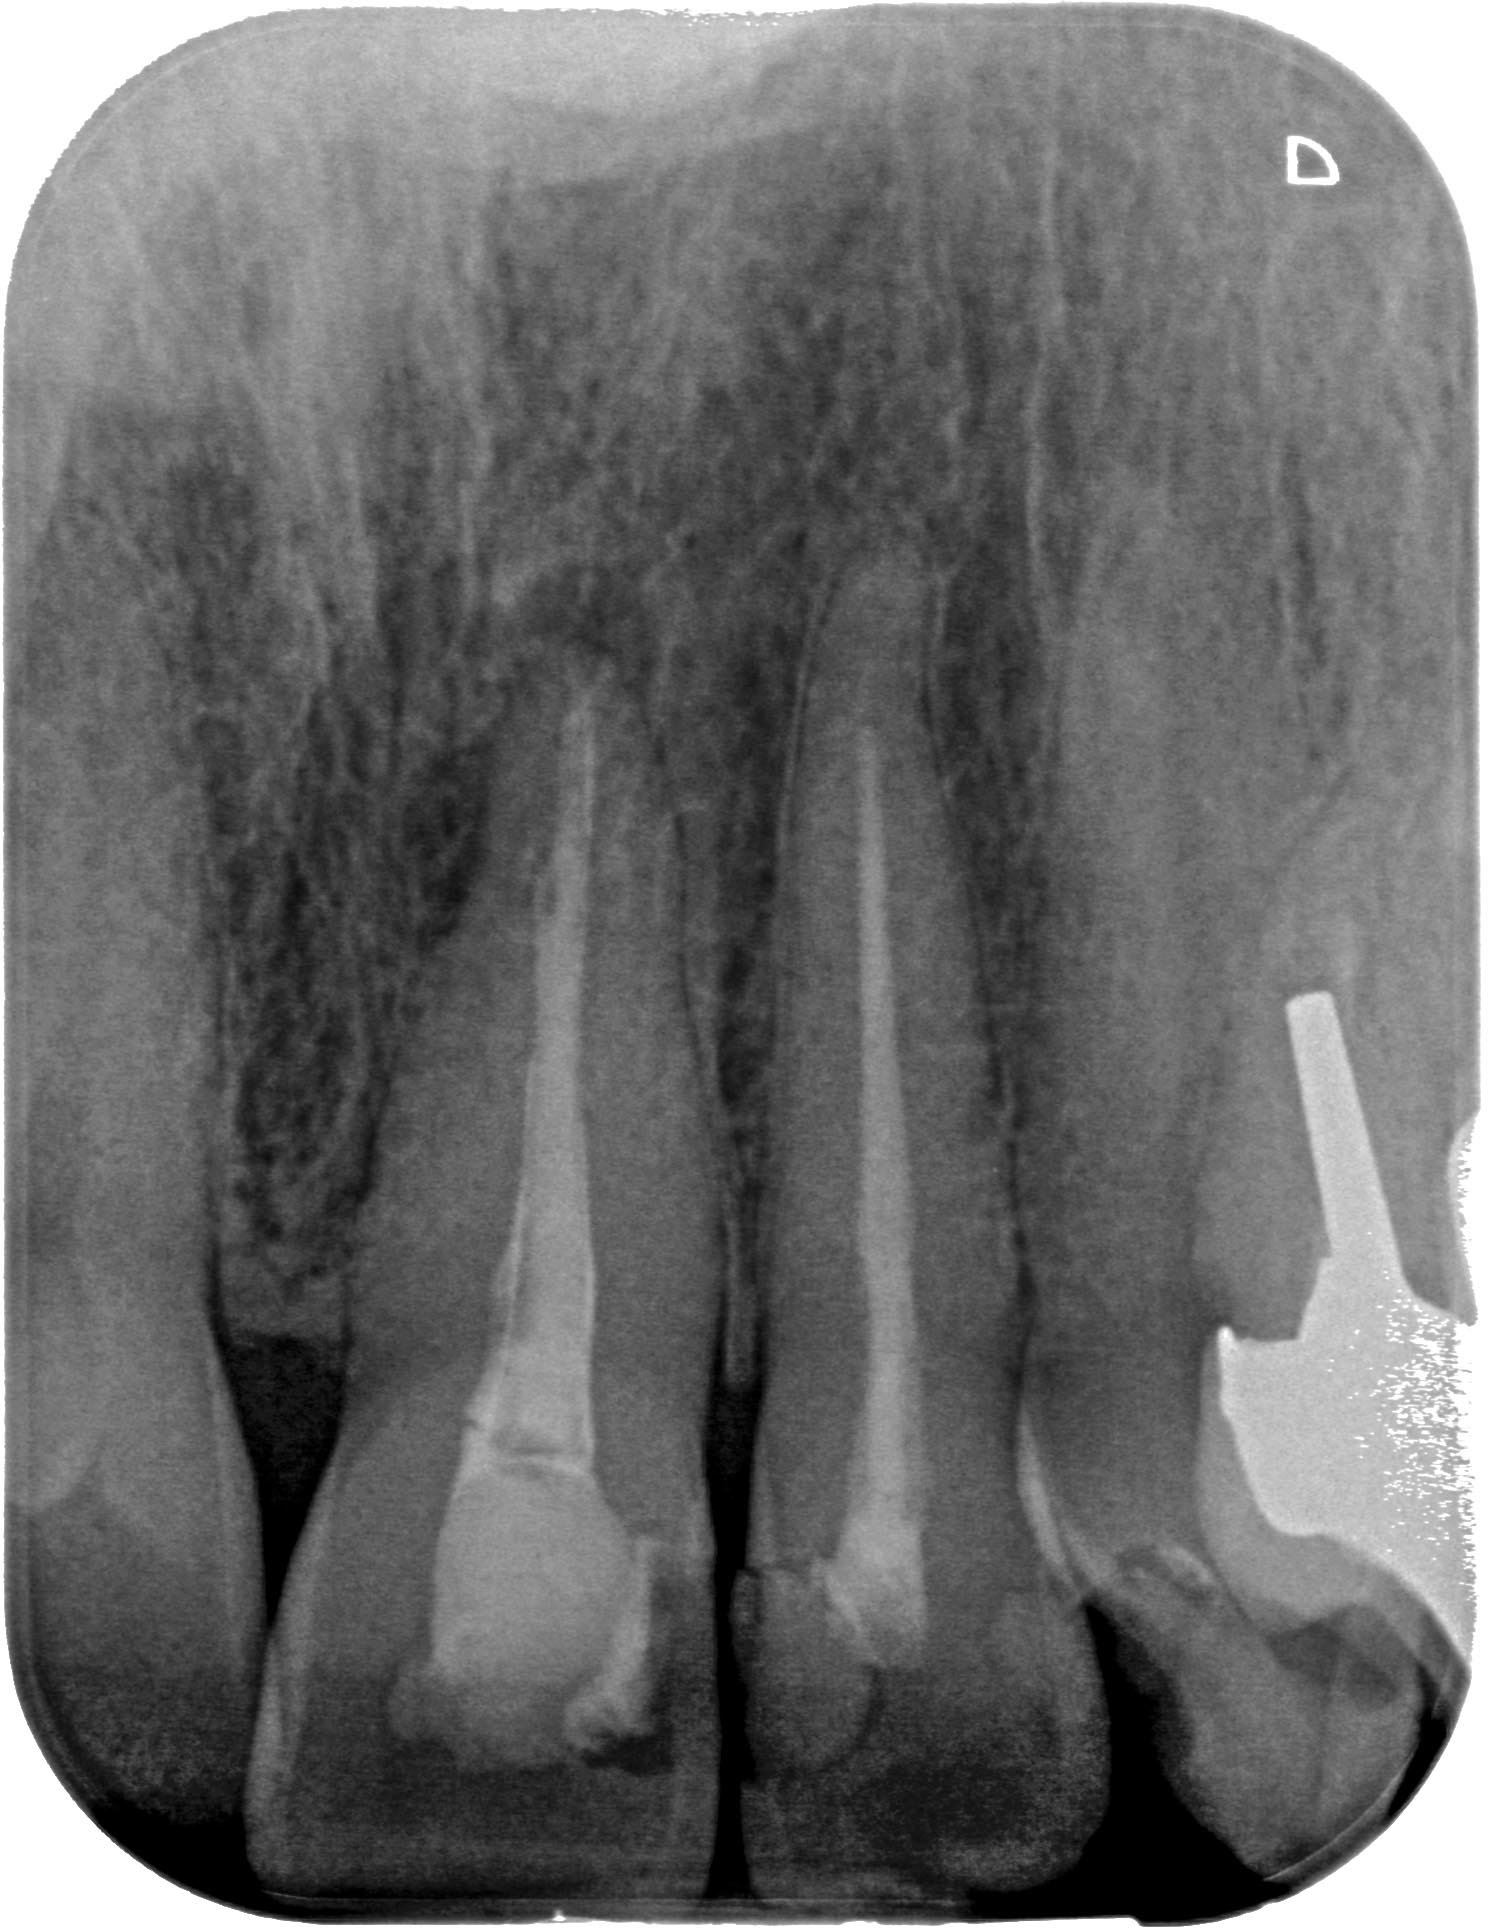

KC_21 (1 von 1) Veröffentlicht 21. Januar 2016 am 1499 × 1928 in Seitenkanal – Dejavu 21 Zustand vor WF- Revision